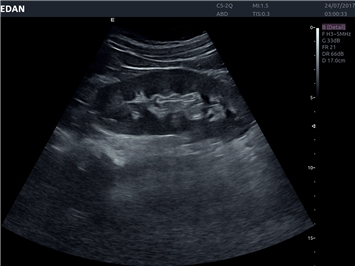

• Автоматизированные измерения в акушерстве

• Акушерства и гинекологии

Объемное сканирование:

Да